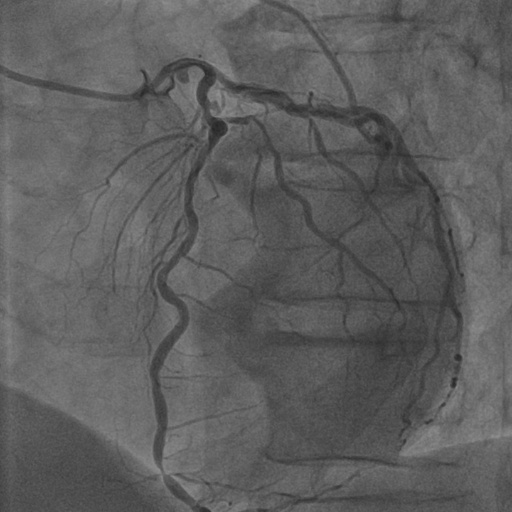

| Image | Ground truth | Video frame | Ground truth | Video frame | Ground truth |

| XCAD [33] | CADICA [19] | Our XACV dataset | |||

4.1 XACV Dataset

We collect 111 complete records of coronary artery X-ray videos, encompassing the injection, flow through the blood vessels around the heart, and dissipation of the contrast agent. Subsequently, we establish the XACV (X-ray Angiography Coronary Video) dataset. Each video consists of varying numbers of high-resolution coronary artery X-ray images. We invite experienced radiologists to annotate the vascular regions, focusing on one or two frames where the contrast agent is most prominent in each video. The XCAD dataset contains only a single image, and the CADICA video dataset does not provide corresponding ground truth. Therefore, in the following experiments, we conduct all the analyses on our collected XACV dataset and the corresponding GT for each sequence. In Figure 5, we show that compared to other publicly available datasets, XCAD [33] and CADICA [19], our dataset exhibits finer annotations in the vascular regions, providing an advantage for future related tasks. The development and use of our dataset have been approved by our institution’s IRB.